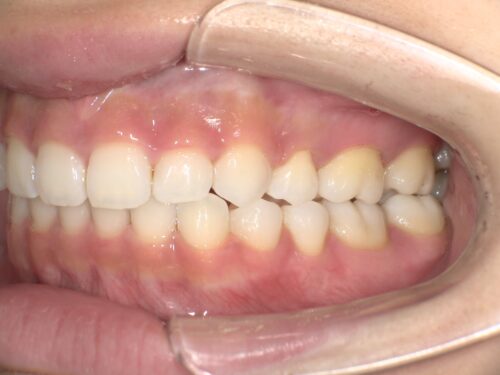

治療後・左側の写真

治療後・右側の写真

横から見ても、上下の前歯の位置関係がしっかり改善されているのが分かります。治療前と比べると、口元の印象がかなり変わりましたね。